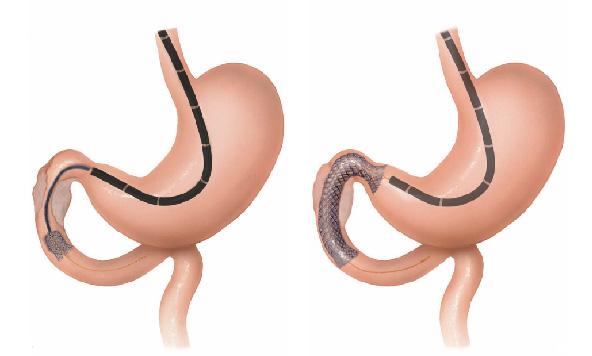

Pacientes que têm o objetivo de emagrecer, podem ter como alternativa a passagem de um balão intragástrico. A passagem do balão é realizada por endoscopia e o procedimento dura cerca de 20 a 30 minutos.

Passagem de Balão Intragástrico

1. O balão intragástrico é introduzido desinsuflado durante a endoscopia e colocado no estômago.

2. Um líquido azul (azul de metileno diluído em soro fisiológico) é colocado dentro do balão através de uma válvula. O volume varia entre 500-700 ml.

3. O aparelho de endoscopia é removido e o balão intragástrico pode ser deixado por um período de até 6 meses.

Como funciona o balão intragástrico?

O balão intragástrico ocupa um espaço dentro do estômago e o paciente fica com sensação de plenitude e saciedade precoce. Em outras palavras, sobra menos espaço para os alimentos, diminuindo o volume ingerido nas refeições.

Pacientes que têm o objetivo de emagrecer, podem ter como alternativa a passagem de um balão intragástrico. A passagem do balão é realizada por endoscopia e o procedimento dura cerca de 20 a 30 minutos.

Passagem de Balão Intragástrico

1. O balão intragástrico é introduzido desinsuflado durante a endoscopia e colocado no estômago.

2. Um líquido azul (azul de metileno diluído em soro fisiológico) é colocado dentro do balão através de uma válvula. O volume varia entre 500-700 ml.

3. O aparelho de endoscopia é removido e o balão intragástrico pode ser deixado por um período de até 6 meses.

Como funciona o balão intragástrico?

O balão intragástrico ocupa um espaço dentro do estômago e o paciente fica com sensação de plenitude e saciedade precoce. Em outras palavras, sobra menos espaço para os alimentos, diminuindo o volume ingerido nas refeições.